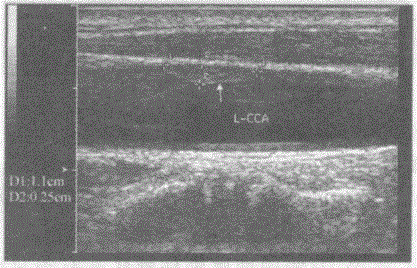

问题 临床资料:男,56岁,常规体检,确诊高血压、糖尿病5年。 超声综合描述:双侧颈总动脉中内膜厚度0.13cm,左侧颈总动脉中段管腔内可见1.1cm×0.25cm中等回声,后方无声影。 超声提示:

选项 A.双侧颈动脉粥样硬化 B.双侧颈动脉粥样硬化并左颈总动脉中段软斑形成 C.双侧颈动脉粥样硬化并钙化斑形成 D.颈动脉正常声像图

答案 B